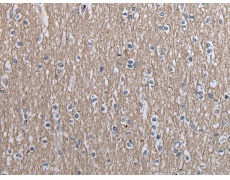

IHC positive control: |

Human brain |

IHC Recommend dilution: |

30-150 |